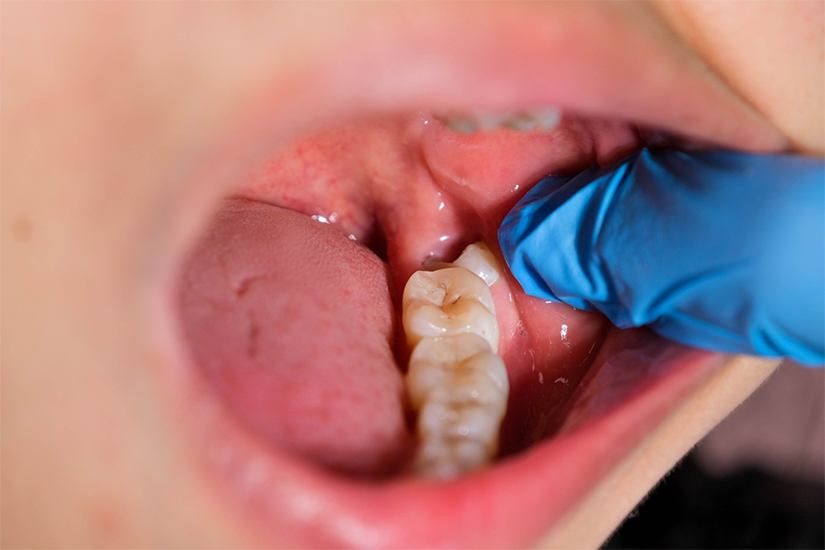

Deși există și cazuri în care măselele de minte erup pe arcada dentară fără să provoace probleme, din păcate, majoritatea persoanelor se confruntă cu durere ori complicații. „Uneori, ultimii molari nu au destul loc pe arcadă pentru a erupe, iar acest lucru îi determină să se poziționeze greșit. Acest lucru poate cauza atât o mușcătură greșită, cât și aglomerarea dinților. Astfel, pacientul se poate confrunta cu disconfort sau chiar cu durere”, explică Dr. Laura Nicolae Ferenț, medic dentist, specialist în chirurgie orală.

De asemenea, măseaua de minte poate erupe deja cariată și, pe lângă disconfortul provocat de această afecțiune, poate dăuna dinților cu care intră în contact la nivelul osos, și anume molarii de 12 ani.

Durerea de măsea de minte poate apărea atât înainte ca ea să erupă pe arcada dentară, cât și după ce aceasta se poziționează lângă dinții vecini. „Molarii de minte pot să creeze probleme chiar și în interiorul osului, înainte să erupă. De exemplu, pot pune presiune pe dinții vecini, ducând la înghesuirea lor. De asemenea, ei pot cauza resorbții ale rădăcinilor dinților din față sau apariția anumitor chisturi sau infecții ale gingiei. Măselele de minte se pot caria cu ușurință, deoarece poziționarea lor duce la reținerea resturilor alimentare”, adaugă dr. Laura Nicolae Ferenț, medic dentist, specialist în chirurgie orală.